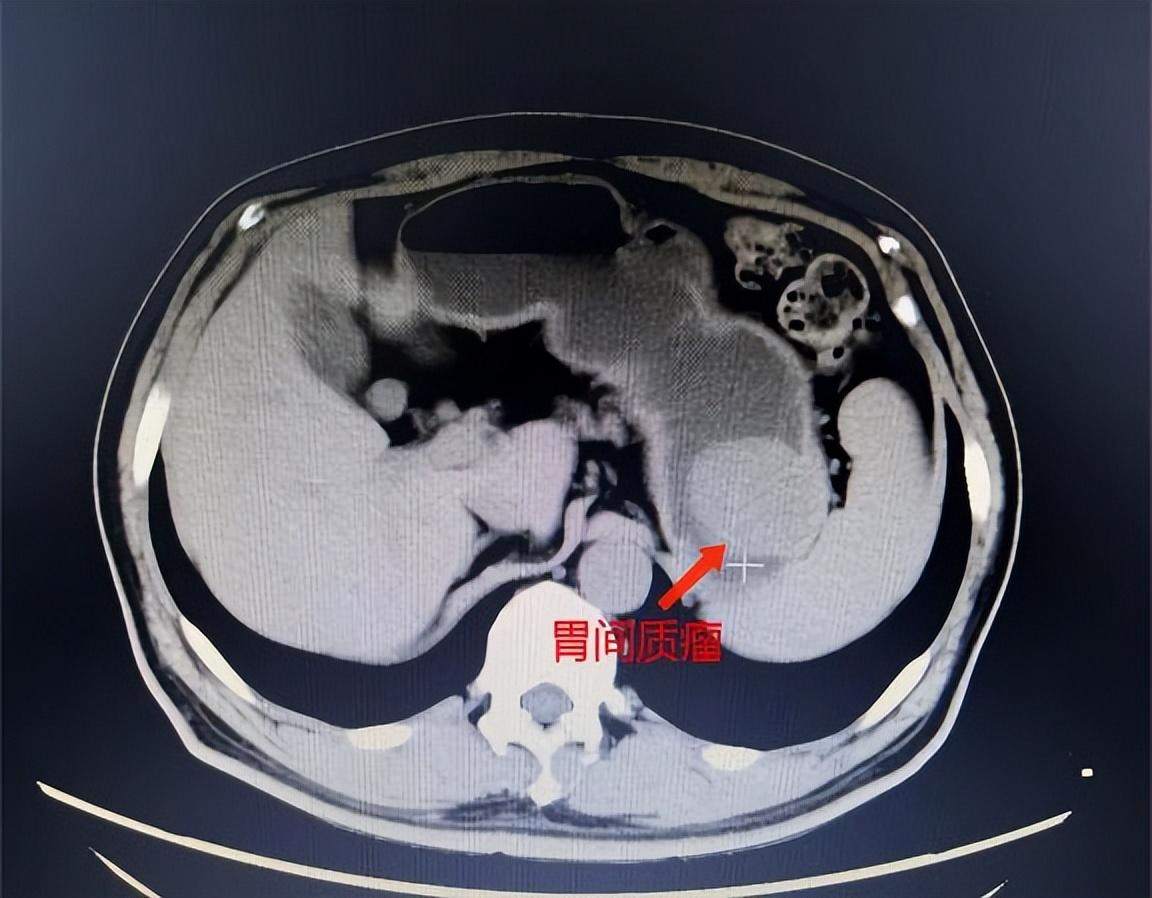

患者周某,女,49岁,1月前外院胃镜体检发现胃体长了一个约2.0×1.5cm的肿瘤,这可把她吓得不轻,急忙赶到深圳禾正医院就诊。消化内科程飞医生在看了周女士的胃镜报告后,考虑具有内镜下切除指征,建议住院进一步评估诊治。完善超声胃镜及上腹低张CT,考虑病变起源于固有肌层,胃腔内外生长,综合判断考虑很大可能是间质瘤。

胃肠道间质瘤又称为胃肠道基质瘤(GIST),主要是基因突变而造成的细胞癌化、增生,胃部发作大约占了60~70%,小肠则是20~30%,其他大肠、直肠、食道则在5%左右。但一般癌症多生长在表皮黏膜细胞,胃肠道间质瘤则生长在肌肉层,容易误诊为其他的组织肉瘤。